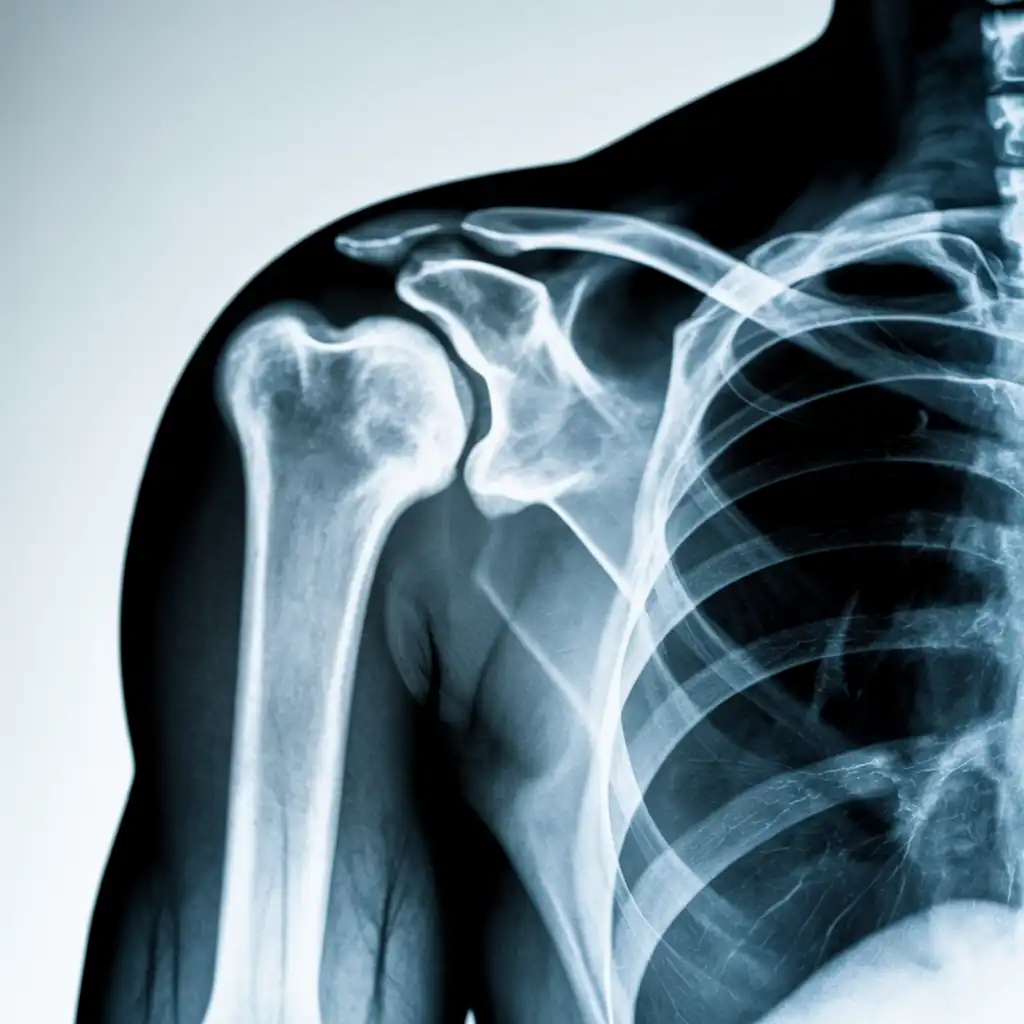

Il professionista entra con apparecchiature a basso dosaggio e schermi protettivi: bastano 2 × 2 m di spazio vicino al letto o alla poltrona. In pochi minuti acquisisce immagini HD, proprio come in un reparto ospedaliero.

Le immagini (formato DICOM) vengono caricate su un server crittografato e inviate immediatamente al radiologo. Se servono scatti aggiuntivi, il tecnico resta in collegamento video per eseguirli al volo.

Il medico radiologo analizza le immagini e firma il referto digitale all’istante. Ricevi il referto cartaceo e le immagini su chiavetta USB consegnati direttamente a casa tua subito dopo l'esame.

Usiamo le stesse apparecchiature certificate CE dei reparti ospedalieri, calibrate regolarmente. I referti sono validi per visite specialistiche, pronto soccorso e pratiche assicurative, e restano archiviati per 10 anni per ogni esigenza futura.